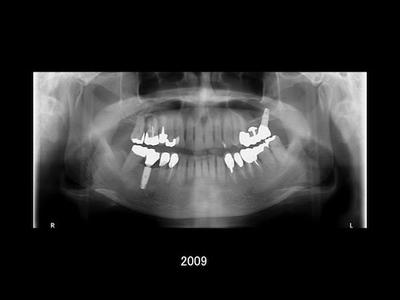

その後の治療と経過

治療経過にご満足いただけたこともあり、

- 1997年:銀歯をセラミックへ変更(審美目的)

- 2004年:外傷により喪失した左上奥歯に Xive インプラントを埋入

と、継続してさまざまな治療をお任せいただきました。

19年間の経過観察より

治療開始から現在まで、およそ19年が経過しました。 これまでの観察では、インプラント周囲の骨の状態も安定しており、セラミックの破折もなく、良好な状態を保っています。

もちろん良好な状態が続いている背景には、患者さんご自身による丁寧な日々のケアがあります。 加えて、3ヶ月に一度のチェックを通じて継続的に口腔内の変化を把握し、必要なタイミングで処置を行えたことも良かったのではないかと感じています。